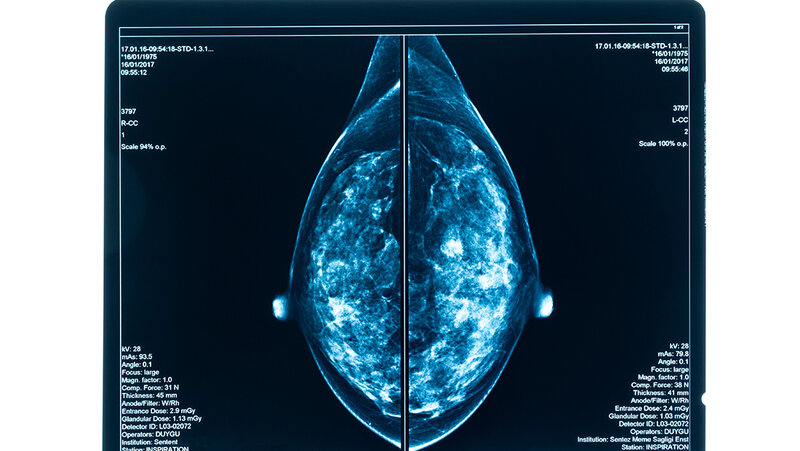

Um die Sicht der Patientinnen und Patienten auf eine Krebsbehandlung zu ermitteln, werden in onkologischen Studien patientenberichtete Zielgrößen (Patient-reported outcomes, kurz PRO) erhoben – leider oft zu kurz, etwa nur bis zu dem Zeitpunkt, zu dem im Röntgenbild ein Wachstum des Tumors angezeigt wirdund es zum Behandlungsabbruch kommt. So ließen sich zum Beispiel die Auswirkungen des im Röntgenbild dargestellten Progresses oder auch langfristige Nebenwirkungen der Krebstherapie auf das Leben der Betroffenen nicht sicher einschätzen, beklagt das IQWiG. Begründet werde das mit organisatorischen Schwierigkeiten oder mit dem Desinteresse der Betroffenen an einer langfristigen Nachverfolgung. „Aber stimmt das überhaupt."